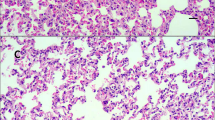

First, H&E staining was performed to observe the abnormalities of gross features in the lungs after chlorine exposure under a light microscope. As shown in Fig. 1A-D, the rats in the NC group displayed normal appearance and no other histological alteration was observed. In contrast, the lung tissues collected from the group expose to chlorine exhibited marked histopathologic changes, such as alveolar wall thinness, edema, hemorrhage and interstitial infiltration by neutrophils. The airway pathology led to abnormalities in the lung parenchyma with alternating areas of emphysema and atelectasis. Thus, the ALI model had been successfully constructed. Applying this model, the ROS accumulation was measured by DHE. This probe was oxidized to form intermediate probe-derived radicals that were successively oxidized to generate the corresponding fluorescent products [17]. The results demonstrated that ROS level was significantly increased in chlorine-treated group (P<0.05) (Fig. 1E-F).

Pathologic changes and ROS accumulation in rats exposed to chlorine. A H&E staining in the lungs of rats in NC group (× 200); B H&E staining in the lungs of rats in NC group (× 400); C H&E staining in the lungs of rats in chlorine group (× 200); D H&E staining in the lungs of rats in chlorine group (× 400); E Confocal microscopy of the lung tissue (× 600); F ROS production measured using DHE. Data are presented as mean ± S.D. (n = 3). *P < 0.05 compared with the normal group. H&E: hematoxylin and eosin; NC: normal control; DHE: Dihydroethidium